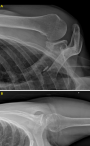

Case 1: patient was reassessed 12 months after surgery, he was pain free, physical activities could be resumed without restriction at same level as before the onset of symptoms. Active range of motion was identical to passive range of motion: antepulsion 180°, abduction 170°, external rotation 180°, external rotation 290°, internal rotation T8. No apprehension or hyperlaxity was detected during the clinical examination or on questioning. Constant score was 99. SSV score was 95. X-rays documented integration of the bone graft into scapular neck (Figure 4).

Case 2: patient was reassessed 13 months after surgery, he was pain free, physical activities could be resumed without restriction at same level as before the onset of symptoms. Active range of motion was same as passive: antepulsion 180°, abduction 170°, external rotation 140°, internal rotation T7. No apprehension or hyperlaxity was evident during clinical examination or on questioning. Constant score was 100. SSV score was 95. X-rays documented integration of bone graft into scapular neck (Figure 5).

Figure 4: (A,B) X-rays at 12 months post-operatively (lamy side and front)

Figure 5: (A,B) X-rays at 13 months after surgery (front and axillary side)